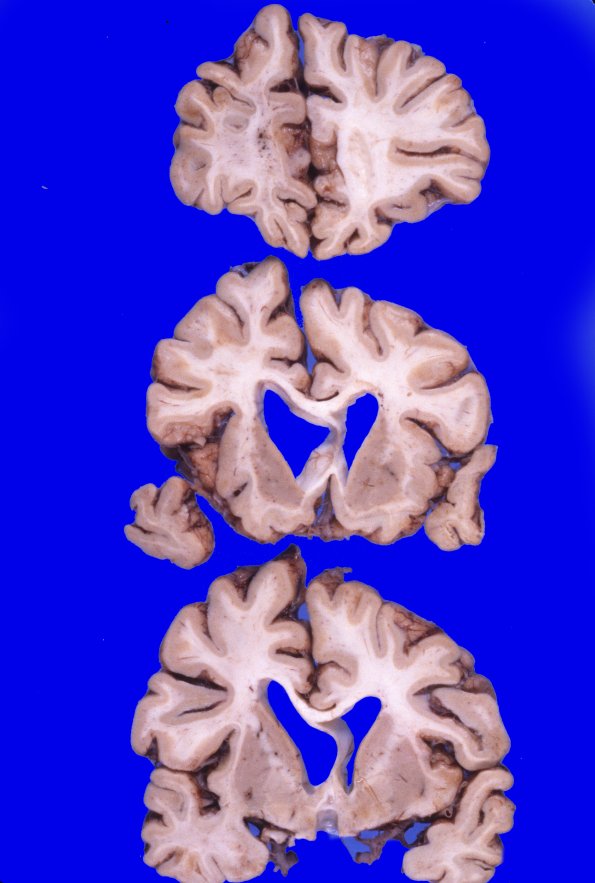

7A3-7 Coronal sections confirm the degree of diffuse cortical atrophy with narrow gyri and wide sulci with a large amount of ventricular dilatation and blunting. The cerebral white matter is diffusely firm to palpation. The corpus callosum is extremely thin.